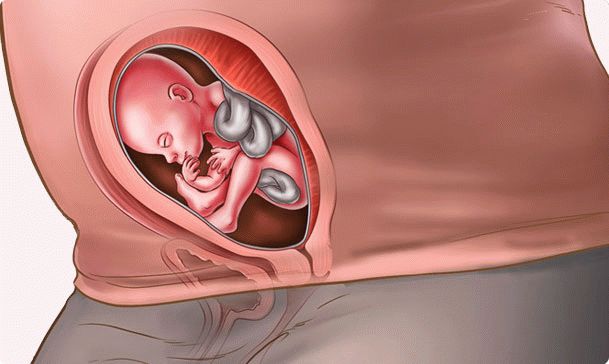

Agora, a principal tarefa do feto é crescer e ganhar peso. O garoto parece um homenzinho. Em proporções do corpo, ele já se assemelha a um recém-nascido. Se seu bebê está destinado a nascer com pêlos na cabeça, então nessa época eles aparecem. Pequenas sobrancelhas e cílios já estão lá, mas é mais provável que não sejam pêlos, mas um cotão leve. Seu filho está constantemente treinando. Pelos sinais do cérebro, o feto literalmente realiza os movimentos de que precisará primeiro.

Nesta semana, a fruta crescerá 18 cm e seu peso atingirá cerca de trezentos gramas. Não se esqueça: seu bebê já ouve, então fale com ele.

Como o bebê está localizado no útero? Como ele quer. Agora não é hora de falar sobre a posição certa ou errada do feto. Há espaço suficiente para as migalhas girarem em todas as direções por mais algumas semanas.